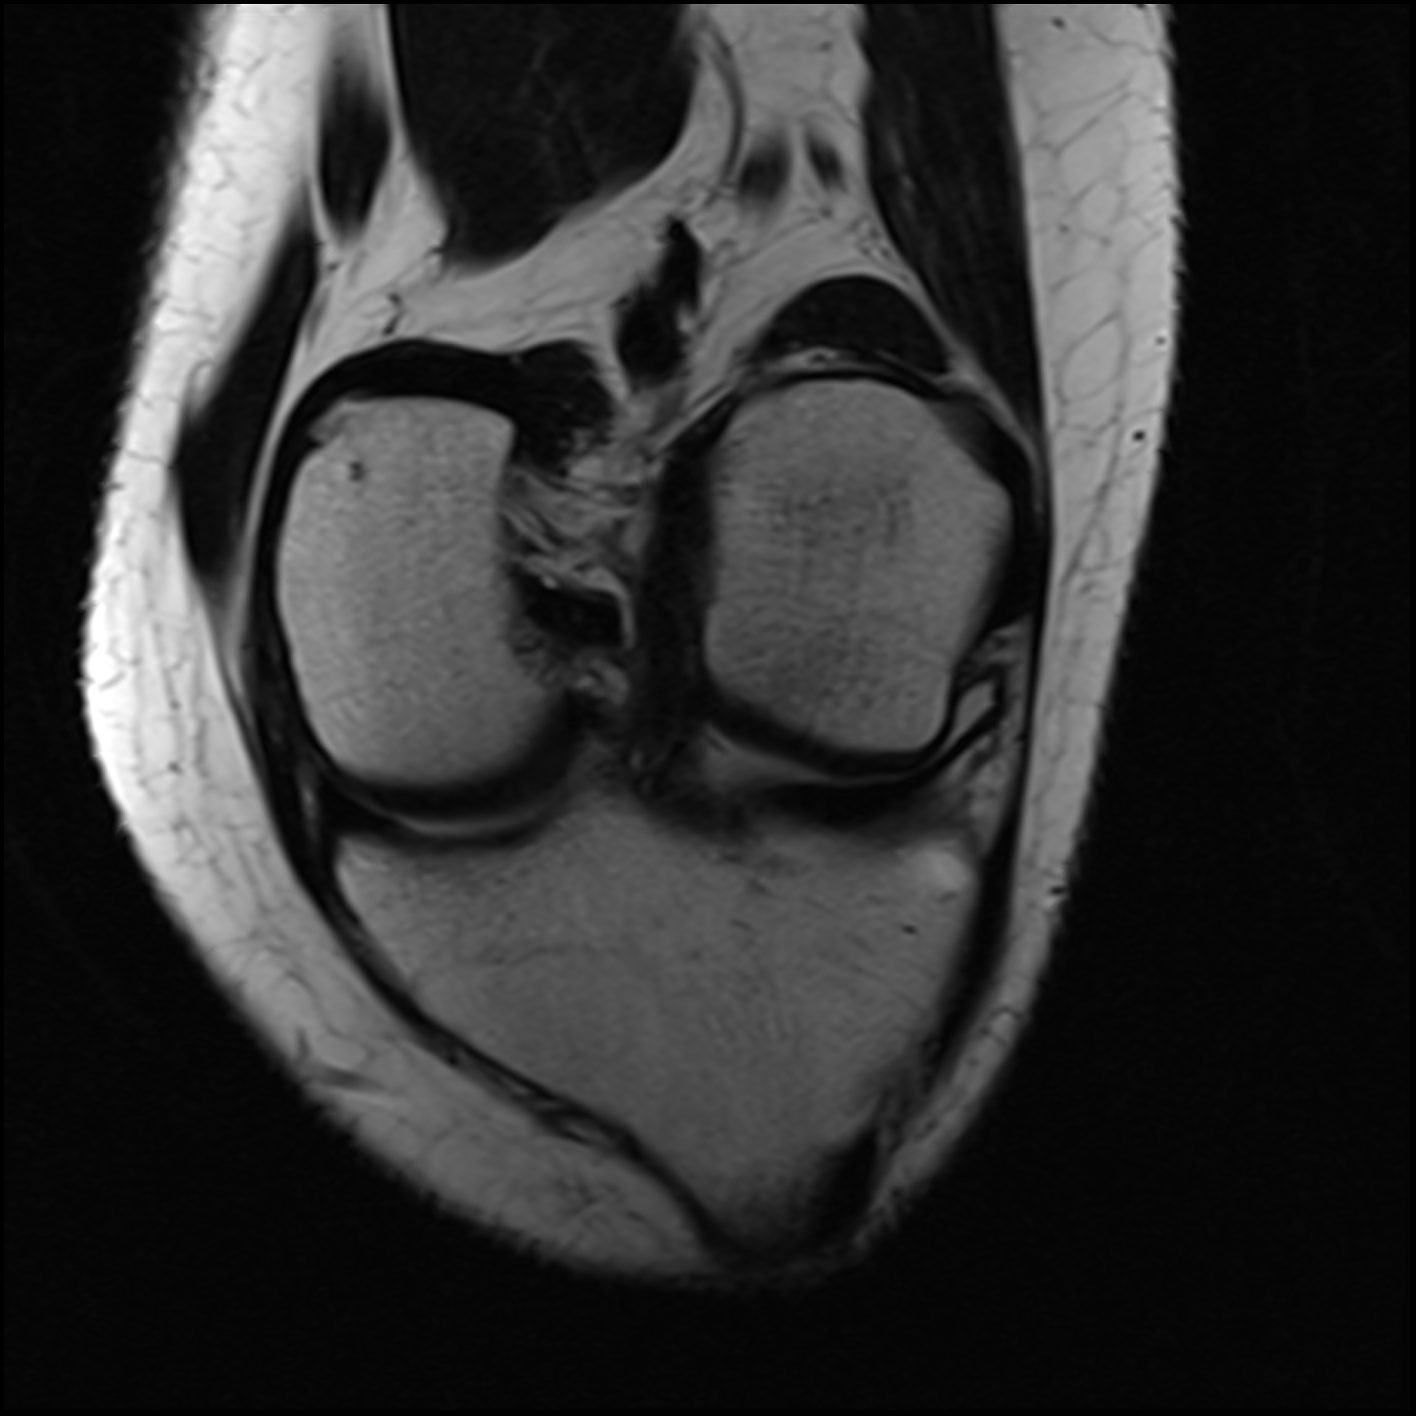

March 2019: Trampoline injury to right knee causing ACL tear, meniscus tear

March 2019: MRI 1

June 2019: MRI 2

December 2019: MRI 3

June 2020: MRI 4

March 2019 MRI

IMPRESSION:

- Complete rupture proximal third anterior cruciate ligament with pivot shift

pattern of bone injuries lateral compartment and contrecoup bone contusion

medial tibial plateau. Joint hemarthrosis. - Complex tear lateral meniscus with inferiorly flipped flap tear extending

into the popliteal hiatus. - Complex tear medial meniscus with outwardly extruded tears of the posterior

horn and body. - Low-grade sprains medial collateral ligament and medial posterior oblique

ligament. - Low-grade sprains fibular collateral ligament and anterolateral ligament.

Intermediate to high-grade sprain popliteofibular ligament and arcuate ligament. - Grade 1 strains vastus lateralis, short head biceps, sartorius, soleus,

popliteus and anterior compartment muscles.

December 2019 MRI

IMPRESSION

- Medial: Nondisplaced horizontal longitudinal tear extending obliquely to the

undersurface of the meniscal body and posterior horn segments. No chondral erosion or thinning. Intact root ligaments. - Intact anterior cruciate ligament. Normal posterior cruciate ligament. Intact medial

lateral supporting structures. - No joint effusion or synovitis. No periarticular muscle injury. No osseous contusion

or stress injury. Minimal fluid in the semimembranosus-medial gastrocnemius bursa. No

frank Baker's cyst.

June 2020 MRI

- Healed femoral-sided ACL tear with partial attenuation of the proximal ACL fibers.

- Progressive healing of horizontal oblique tear of the medial meniscus posterior horn.

- Chronic inferiorly displaced meniscal flap tear at the lateral meniscus posterior

horn-root junction, less conspicuous than on prior MR imaging. Resolution of previously

noted horizontal longitudinal tear of the body-posterior horn segments. - No new evidence of internal derangement. No acute osseous abnormality.